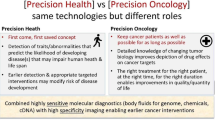

Considering the above discussion, we propose a “core protocol” for WB-MRI composed of T1 weighted GRE sequences together with T2 weighted TSE sequences and DWI, as described in Table 3 and in Fig. 1. Anatomical coverage, field of view and slice thickness should be homogeneous across the sequences, in order to facilitate image correlation and interpretation. If available, automatic image composing should be enabled on the scanner during acquisition, in order to produce stacks for each type of image generated without the need for manual intervention.

Core protocol. This image summarizes the main pulse sequences included in the WB-MRI protocol for cancer screening. The study should cover from head to pelvis. T1 weighted images are acquired with a gradient recalled echo (GRE) sequence, preferably with Dixon technique, to obtain four different sets of images (in-phase, opposed-phase, water-only, fat-only) and to allow the calculation of the relative fat-fraction (rF%) map. T2 images are acquired with a single-shot fast spin echo (FSE) sequence. Diffusion-weighted images (DWI) should be acquired with at least two b values in order to obtain the corresponding apparent diffusion coefficient (ADC) map. Maximum intensity projections (MIP) should be reconstructed from the highest b value DWI images